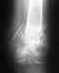

Re: Консолидирующийся перелом внутренней лодыжки

Разговор беспредметный. Без собственно снимков какие могут быть комментарии?